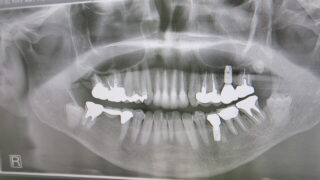

骨吸収

数年ぶりに来院された患者様でしたがパノラマレントゲンを撮ると下顎左側6番に骨透過像が見られます。CTで確認すると、かなり大きくおそらく手前のインプラントもだめにしてしまいます。この場合は抜歯しかありません。定期的に来院して頂けたらかわってい...